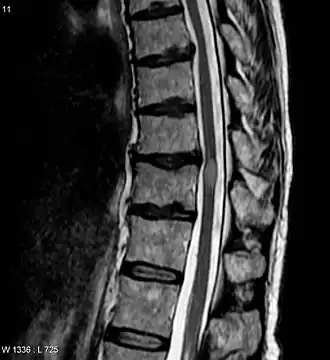

Imagem por ressonância magnética (IRM) mostrando uma lesão de mielite transversa (exame realizado 3 meses após a recuperação do paciente).